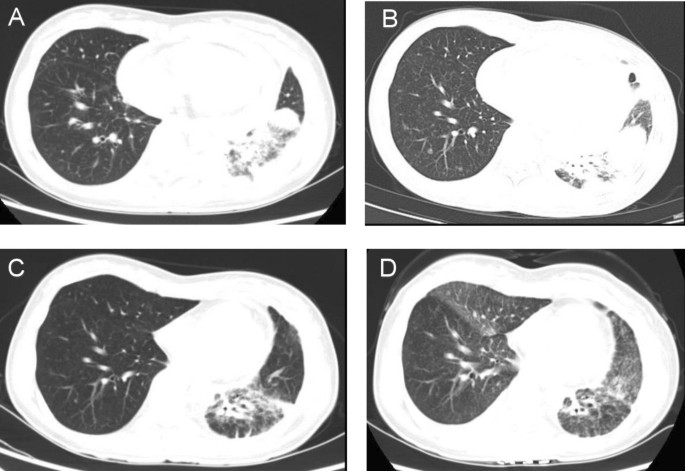

CT scan showed a 1.4 cm × 1.3 cm mass in the right upper lobe (RUL) (Fig. 1 a) and a right lower lobe (RLL) mass-like consolidation (Fig. 1 b). Histopathologic examinations of CT-guided-percutaneous needle biopsy (PCNB) of the RUL mass revealed adenocarcinoma (ADC) (Fig. 2 a–c) with clinical staging cT1bN0M0 on ultrasonic-guided transbronchial needle biopsy (EBUS-TBNB) and fluorodeoxyglucose F18-positron emission tomography (FDG-PET) scan. RLL mass showed no metabolism on the FDG-PET scan. The FEV 1 was 56% of the predicted value. We planned a lobectomy for the RUL cancer and a follow-up for the RLL mass. However, the patient refused to undergo surgery and was treated with stereotactic radiosurgery (SRS) on the RUL mass in January 2019. The RLL mass-like consolidation did not show any changes on the follow-up chest CT or FDG-PET scan in November 2019.

Chest CT scans. a A mass on the RUL of the first adenocarcinoma (arrow). b A mass on the RLL at the same time of the first cancer diagnosis (arrow). c Increased RLL mass six months later (arrow). d Further increased RLL mass after five months (arrow). e New nodule on the peripheral RLL (arrow). f–h Development and increase of the lymph node (arrow). i Bronchoscopic finding showing LLL anterobasal segment obstruction (arrow). j Lymph node enlargement on the EBUS. CT, computed tomography; RUL, right upper lobe; RLL, right lower lobe; LLL, left lower lobe; EBUS, endobronchial ultrasound

In June 2020, the RLL mass-like consolidation was found to have increased on a chest CT scan (Fig. 1 c). PCNB of the RLL mass was performed, and histologic examination revealed anthracofibrosis. Five months later, the RLL mass increased further (Fig. 1 d), and a new nodule appeared at the periphery of the RLL (Fig. 1 e). PCNB was performed again on the same RLL mass (Fig. 1 d), and histological examination demonstrated squamous cell carcinoma (SCC) (Fig. 2 d–f). There was no metastasis except for hypermetabolism of the new nodule in the RLL periphery (Fig. 1 e) on the FDG-PET scans. We could not perform a biopsy for the new peripheral nodule (Fig. 1 e) due to cystic changes. We concluded the clinical staging of the RLL SCC as cT3N0M0 on the EBUS-TBNB and PET scan. SRSs were performed separately for the RLL SCC and the new RLL peripheral nodule, respectively in February 2021.

We performed chest CT scan for surveillance of lung cancer. Five months later after 2nd SCC diagnosis, a new nodule emerged at the left lower lobe (LLL) (Fig. 1 f, g). Two months after that, the nodule increased further (Fig. 1 h). Bronchoscopy showed new total obstruction of the anterobasal segmental bronchus of the LLL (Fig. 1 i). Histologic examinations of bronchial biopsy and EBUS-TBNB (Fig. 1 j) for LLL lesions demonstrated small cell lung carcinoma (SCLC) (Fig. 2 g–i). Clinical staging was limited stage. The patient was treated with chemotherapy (etoposide/carboplatin) and concurrent thoracic radiation.